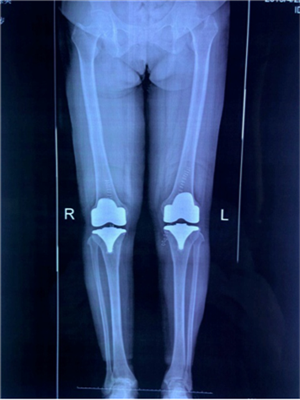

67歲的徐女士是陜北定邊縣人,10年來,她因?yàn)殡p膝關(guān)節(jié)疼痛,行走困難,不能上下樓梯,更無法像常人一樣下蹲,這給徐阿姨和她的家庭帶來了巨大的困擾。經(jīng)多方打聽,徐阿姨慕名找到張富軍主任,張主任詳細(xì)檢查后發(fā)現(xiàn)徐阿姨為雙側(cè)嚴(yán)重的骨關(guān)節(jié)炎并滑膜軟骨瘤病,需要進(jìn)行全膝關(guān)節(jié)置換術(shù)??紤]到患者有多種基礎(chǔ)病合并癥,張主任帶領(lǐng)其團(tuán)隊(duì)認(rèn)真研究后制定了詳細(xì)、周密的手術(shù)方案,做好圍手術(shù)期的準(zhǔn)備,決定采用最新技術(shù)的Vanguard CR E1假體雙膝膝關(guān)節(jié)置換術(shù)。

?。ㄊ中g(shù)前、手術(shù)后對(duì)比)

5月29日,徐阿姨如期進(jìn)行了雙側(cè)全膝關(guān)節(jié)同期置換術(shù)。術(shù)中發(fā)現(xiàn)徐阿姨膝關(guān)節(jié)退變嚴(yán)重,有大量的滑膜軟骨瘤,清除病變后又發(fā)現(xiàn)她前交叉韌帶缺失后交叉韌帶纖細(xì),即決定采用限制性較高的E1 AS墊片,該假體極大的提高了手術(shù)安全性,降低了手術(shù)風(fēng)險(xiǎn)和創(chuàng)傷,手術(shù)歷時(shí)2小時(shí),患者術(shù)后恢復(fù)良好。手術(shù)后第二天,徐阿姨就可以扶著助步器下地活動(dòng),目前已可以徒步行走、上下樓梯。